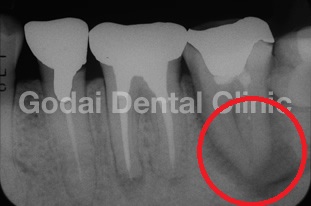

CT撮影を実施することもあります。これも「見える化」の1つです。以下の画像は、CT(3次元)レントゲン(2次元)を使用して同じ患部を撮影した比較画像です。

左側の画像がCTによる撮影で、右側がレントゲンによるものです。

CTで撮影された左の画像では、赤丸で囲んだ部分に黒い影が確認できます。この黒い影は「炎症」を示しています。一方、右のレントゲン画像ではこの黒い影は見えません。これは、レントゲンだけではこのような炎症を見逃してしまうリスクがあることを意味しています。炎症が見逃されると、悪化して最終的には抜歯が必要になる可能性もあります。